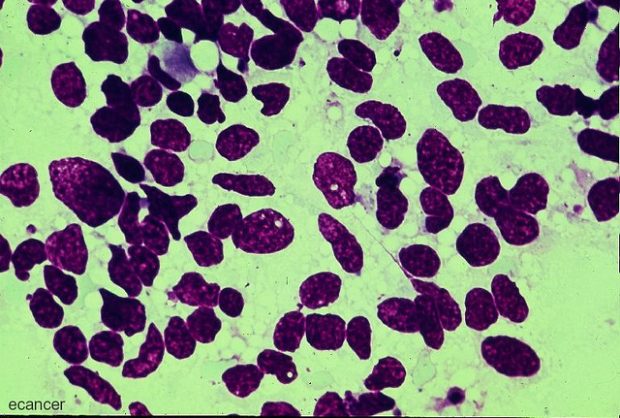

Mit einem raffinierten Täuschungsmanöver wollen Forscher in Israel den Krebs besiegen. Im Tierversuch hat es bereits geklappt. 44 bis 60 Prozent der Tumorzellen starben nach nur einer Behandlung ab. Gleichzeitig verlangsamte sich das Wachstum der übriggebliebenen Zellen. Foto: Small cell lung cancer, ecancer medicalscience, Trojanisches Pferd gegen Krebs Die Wissenschaftler der Universität Tel Aviv haben eine Art Trojanisches Pferd entwickelt, das die Krebszellen dazu bringt, ein Protein zu produzieren, das für sie ein tödliches Gift ist. Dazu ändern sie die Baupläne, die jede Zelle benötigt, um bestimmte Proteine zu produzieren. Die Natur hat es so ein gerichtet, das meist nützliche Bausteine hergestellt werden. Dan Peer, Professor und Direktor des Laboratory of Precision NanoMedicine in Tel Aviv, und sein Team haben jedoch etwas Gegenteiliges im Sinn. Bei Corona hat es schon funktioniert In allen lebenden Zellen befinden sich Ribosomen, die im Wesentlichen winzige Fabriken sind, die Proteine produzieren. Welche Proteine sie herstellen, hängt von den „Bauplänen“ ab, die sie von Boten-RNA-Molekülen (mRNA) erhalten. Diese haben beispielsweise die Biontec-Forscher manipuliert, um einen Impfstoff gegen Covid-19 zu produzieren, indem sie die Viren täuschen. Verhängnisvolle Baupläne für den Krebs Peer und sein Team haben etwas Ähnliches gemacht. Sie entwickelten Baupläne für ein Tumorgift und schoben sie mRNA unter. Diese manipulierten Botenstoffe umgaben sie mit einem Lipid, sodass Nanopartikel entstanden. Diese injizierten sie direkt in Krebszellen. Diese „lasen“ die für sie verhängnisvollen Baupläne und produzierten das Gift, das sie abtötete. Die Krebszellen begingen unwillentlich Selbstmord. Gesunde Zellen werden nicht geschädigt Die Forscher glauben, dass diese gezielte Methode effektiver und nebenwirkungsärmer ist als eine Chemotherapie, die ungewollt viele gesunde Zellen schädigt. „Mit einer einfachen Injektion in das Tumorbett können wir Krebszellen dazu bringen, ‚Selbstmord zu begehen‘, ohne gesunde Zellen zu schädigen“, sagt Peer. „Außerdem können Krebszellen keine Resistenzen gegen unsere Technologie entwickeln, wie es bei einer Chemotherapie oft der Fall ist, weil wir immer ein anderes natürliches Toxin verwenden können.“ Bei den erfolgreichen Tierversuchen wurden keine schädlichen Nebenwirkungen sichtbar. Jetzt werden klinische Tests an Menschen vorbereitet. via Teile den Artikel oder unterstütze uns mit einer Spende. Facebook Facebook Twitter Twitter WhatsApp WhatsApp Email E-Mail Newsletter